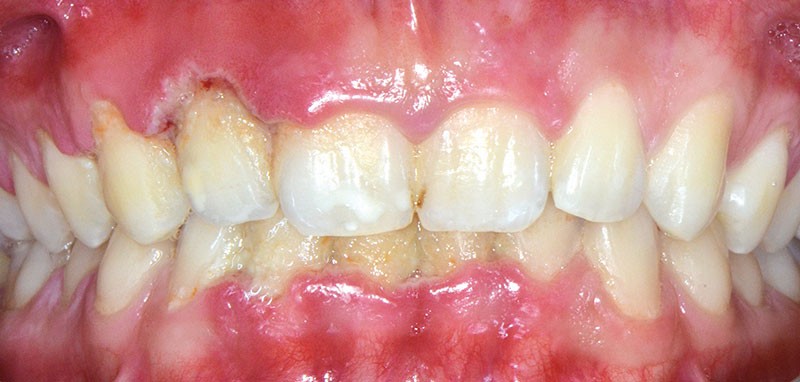

Le diagnostic de la GUN se fonde sur l’association de trois signes cliniques pathognomoniques [3] (fig. 1) :

• la nécrose des papilles gingivales :

les papilles sont les premiers sites à se nécroser, laissant une muqueuse en forme de cratère. La gencive marginale…